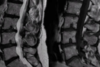

Varon joven con dificultad para la marcha y flexión del tronco. Pérdida de fuerza en el pie

Espondilolistesis istmica de L5-S1

Indicación qx fx toracolumbares

Clínica neurológica progresiva Fragmentos óseos canal medular Cifosis angular >25 grados Pérdida >50% altura vertebral